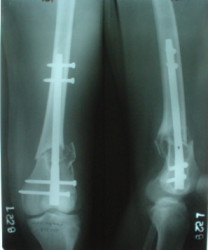

The mobilisation of knee is started immediately from the second day. Weight bearing is permitted as in any other interlocked nailing. That is, Toe touch to start with and within four days, partial to in another two weeks, full weight bearing. Of course that is assuming that the correct size nail has been used. Up to 70 kg body weight, 11no will be good enough and 12mm if more.Usually at the 1st followup, at 6 weeks time, they have full flexion..I

have seen a few surgeons putting in a drain, but I have not found it unnecessary. There has never been any effusion needing active treatment.

Enclosing a recent intraop picture